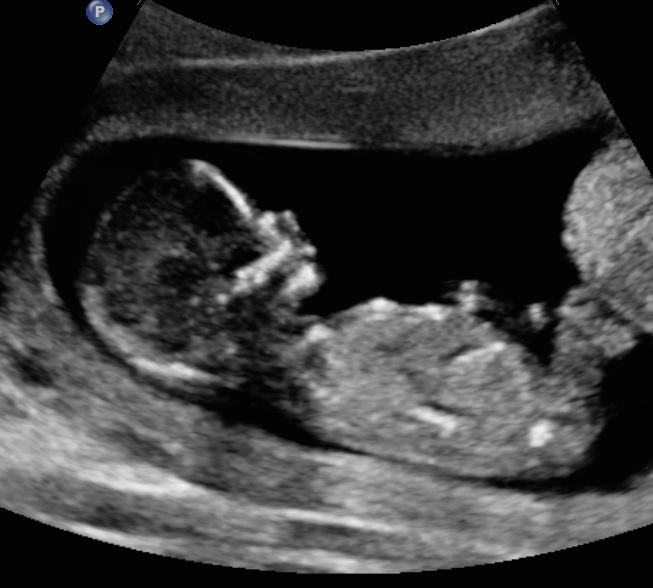

13 weeks 3 days. My first ultrasound. Tech wouldn't take a guess. Id love to know if any of you think girl or boy!!Attachment 25012Attachment 25013Attachment 25014

I'm sorry, I don't see a nub, but will give a boy skull guess just for fun! (not reliable!)

Nope they did a good job keeping that nub hidden from view on the angles they chose.

Not seeing any clue, sorry...